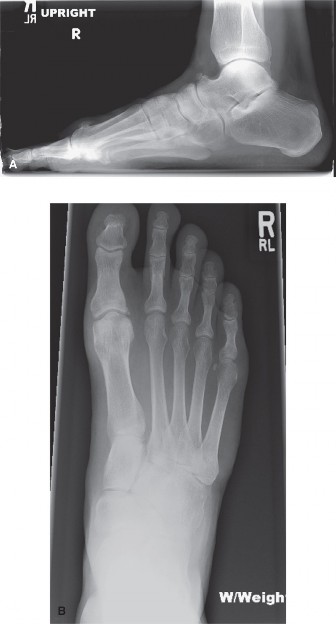

A 54-year-old woman presents to clinic reporting discomfort on the dorsum of her foot with shoewear and pain …

A 60-year-old male presents noting left foot pain of over a year’s duration. He was originally diagnosed with…

A 45-year-old man presents to your office with pain and stiffness in his big toe. He denies any history of tr…